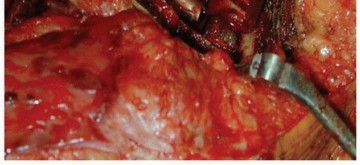

تُعرف جراحة مراجعة مفصل الورك بأنها إجراء جراحي يتم فيه استبدال أحد مكونات مفصل الورك الصناعي أو كلاهما (الدعامة الفخذية أو مكون الحُق) بسبب فشل الزرع الأصلي. على الرغم من النجاح الساحق والموثوقية طويلة الأمد لاستبدال مفصل الورك الكلي الأولي، إلا أن هناك عدة أسباب قد تستدعي إجراء جراحة مراجعة.

تُعد الدعامات الفخذية الأسطوانية غير الأسمنتية المطلية بالمسام بشكل كامل خيارًا علاجيًا متقدمًا وحلاً فعالاً في العديد من حالات مراجعة مفصل الورك. تعتمد هذه الدعامات على تصميم فريد يسمح بنمو العظم داخل سطحها المسامي، مما يوفر تثبيتًا بيولوجيًا قويًا ومستقرًا على المدى الطويل. يعتبر الأستاذ الدكتور محمد هطيف في صنعاء مرجعًا في استخدام هذه التقنية، ملتزمًا بتقديم أحدث وأنجح العلاجات لمرضاه.

يمكن أن يحدث عدم الاستقرار، مثل الخلع المتكرر للمفصل، نتيجة لوضع خاطئ للمكونات أثناء الجراحة الأولية أو بسبب تآكل الأنسجة الرخوة المحيطة.